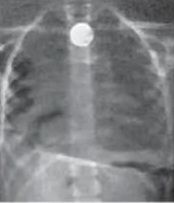

परिजन घबराकर बच्ची को तत्काल शहर के एक निजी अस्पताल ले गए, जहां एक्स-रे जांच में स्थिति गंभीर पाई गई। डॉक्टरों ने बिना देरी किए बच्ची को सिम्स अस्पताल, बिलासपुर रेफर कर दिया। रात के समय सिम्स पहुंचने पर दोबारा किए गए एक्स-रे में साफ हुआ कि सिक्का गले के निचले हिस्से में अटका हुआ है, जिससे बच्ची की जान को खतरा हो सकता था।

रात करीब 12:30 बजे सिम्स के ईएनटी विभाग की टीम ने तुरंत इलाज शुरू किया। डॉक्टरों ने दूरबीन तकनीक (एंडोस्कोपी) की मदद से बेहद सावधानीपूर्वक बच्ची के गले में फंसे सिक्के को बाहर निकाल लिया। यह प्रक्रिया नाजुक थी, लेकिन डॉक्टरों की सतर्कता और टीमवर्क से ऑपरेशन पूरी तरह सफल रहा।